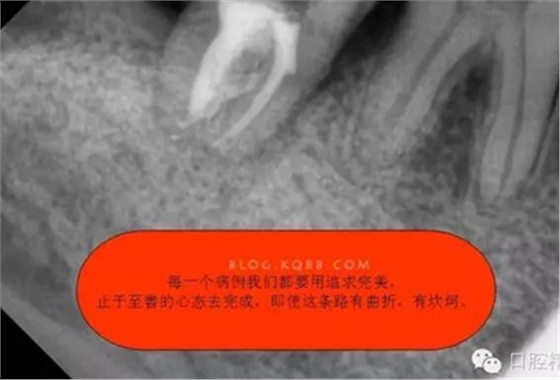

2.這種C型(2型)根管,在治療的過程中,要注意最重要的兩點,一是要在沖洗的過程中用超聲蕩洗,必須用3%次氯酸鈉加雙氧水交替沖洗,因為C型根管是不規(guī)則的,要把不規(guī)則的根管沖洗干凈只有超聲蕩洗才能做到。二是充填的時候,要用熱牙膠充填系統(tǒng),只有這樣根管充填才能充填致密,雖然拍X線片會顯示出與常見根管充填不一樣的顯影,但是不規(guī)則的C型根管充填是這種情況,不要被常規(guī)充填結(jié)果所誤導。